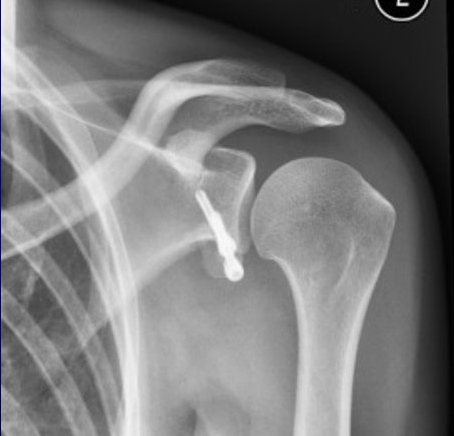

Lararjet(らたるじぇ)法の手術後レントゲンです​

Lararjet(らたるじぇ)法の手術後レントゲン